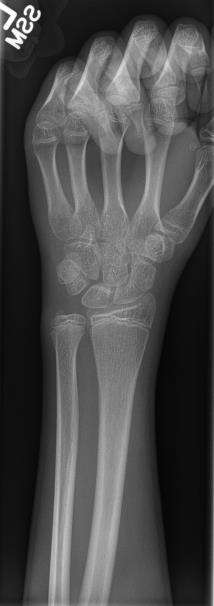

The creation of images by exposing an object to X-rays or other high-energy forms of electromagnetic radiation and capturing the resulting remnant beam (or "shadow") as a latent image is known as "projection radiography." The "shadow" may be converted to light using a fluorescent screen, which is then captured on photographic film, it may be captured by a phosphor screen to be "read" later by a laser (CR), or it may directly activate a matrix of solid-state detectors (DR—similar to a very large version of a CCD in a digital camera). Bone and some organs (such as lungs) especially lend themselves to projection radiography. It is a relatively low-cost investigation with a high diagnostic yield. The difference between soft and hard body parts stems mostly from the fact that carbon has a very low X-ray cross section compared to calcium.

Projection radiography uses X-rays in different amounts and strengths depending on what body part is being imaged:

- Hard tissues such as bone require a relatively high energy photon source, and typically a tungsten anode is used with a high voltage (50-150 kVp) on a 3-phase or high-frequency machine to generate bremsstrahlung or braking radiation. Bony tissue and metals are denser than the surrounding tissue, and thus by absorbing more of the X-ray photons they prevent the film from getting exposed as much.[1] Wherever dense tissue absorbs or stops the X-rays, the resulting X-ray film is unexposed, and appears translucent blue, whereas the black parts of the film represent lower-density tissues such as fat, skin, and internal organs, which could not stop the X-rays. This is usually used to see bony fractures, foreign objects (such as ingested coins), and used for finding bony pathology such as osteoarthritis, infection (osteomyelitis), cancer (osteosarcoma), as well as growth studies (leg length, achondroplasia, scoliosis, etc.).

- Soft tissues are seen with the same machine as for hard tissues, but a "softer" or less-penetrating X-ray beam is used. Tissues commonly imaged include the lungs and heart shadow in a chest X-ray, the air pattern of the bowel in abdominal X-rays, the soft tissues of the neck, the orbits by a skull X-ray before an MRI to check for radiopaque foreign bodies (especially metal), and of course the soft tissue shadows in X-rays of bony injuries are looked at by the radiologist for signs of hidden trauma (for example, the famous "fat pad" sign on a fractured elbow).